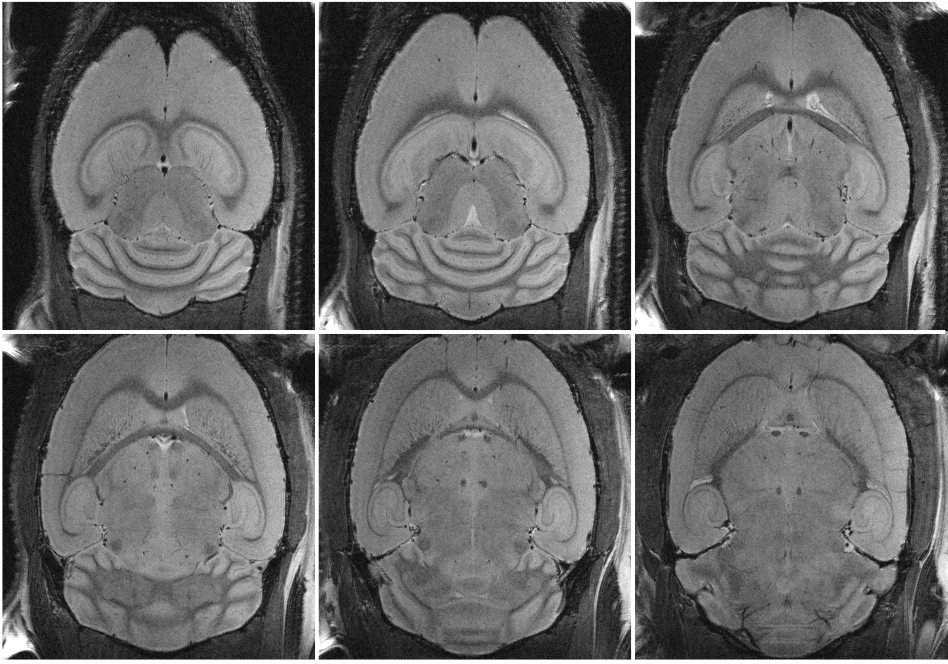

In vivo mouse brain with 29 µm resolution, measured at 15.2 T with MRI CryoProbe. Acquisition details: RARE, resolution: (29 × 29 × 200) µm³, TR: 3.5 s, TE: 25 ms, echoes: 6, slices: 7

In preclinical MRI, cryogenically-cooled MRI CryoProbes [2], provide an additional sensitivity boost [3] and have found widespread use. Combined with UHF MRI, the additional gain is significant and enables highest quality images in reasonable measurement times [4]. Thus, for example, ultra high resolution in vivo mouse brain data can be easily acquired on a preclinical 15.2 Tesla equipped with a MRI CryoProbe.